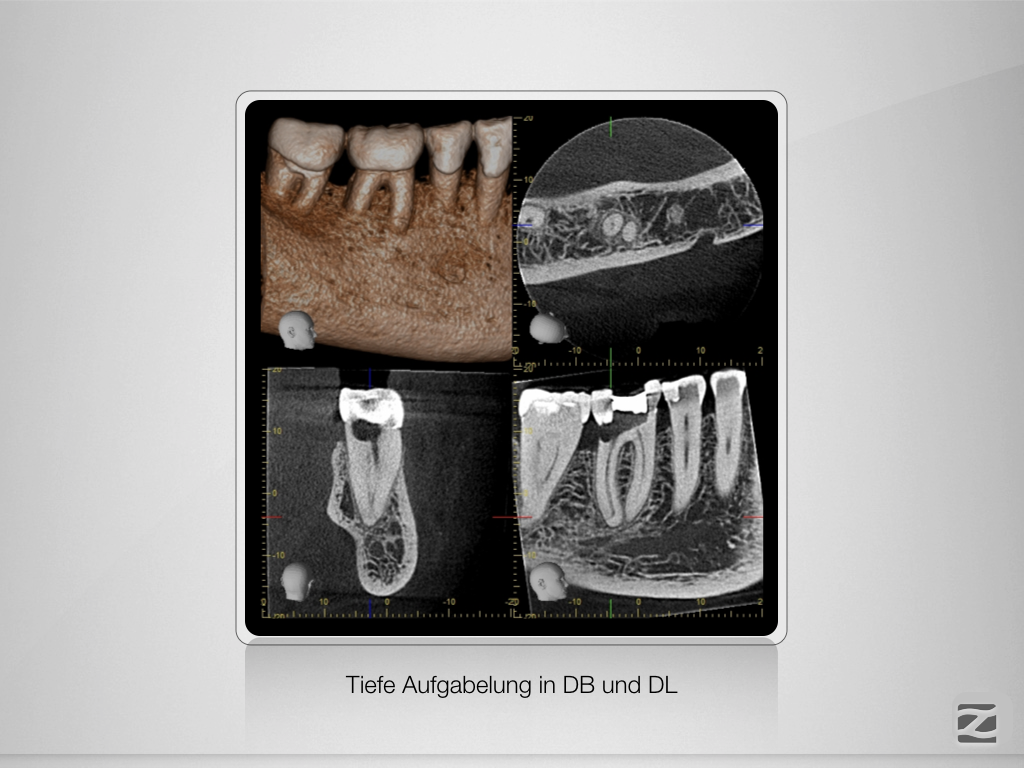

Tiefe Gabelung mit 90 Grad nach distal